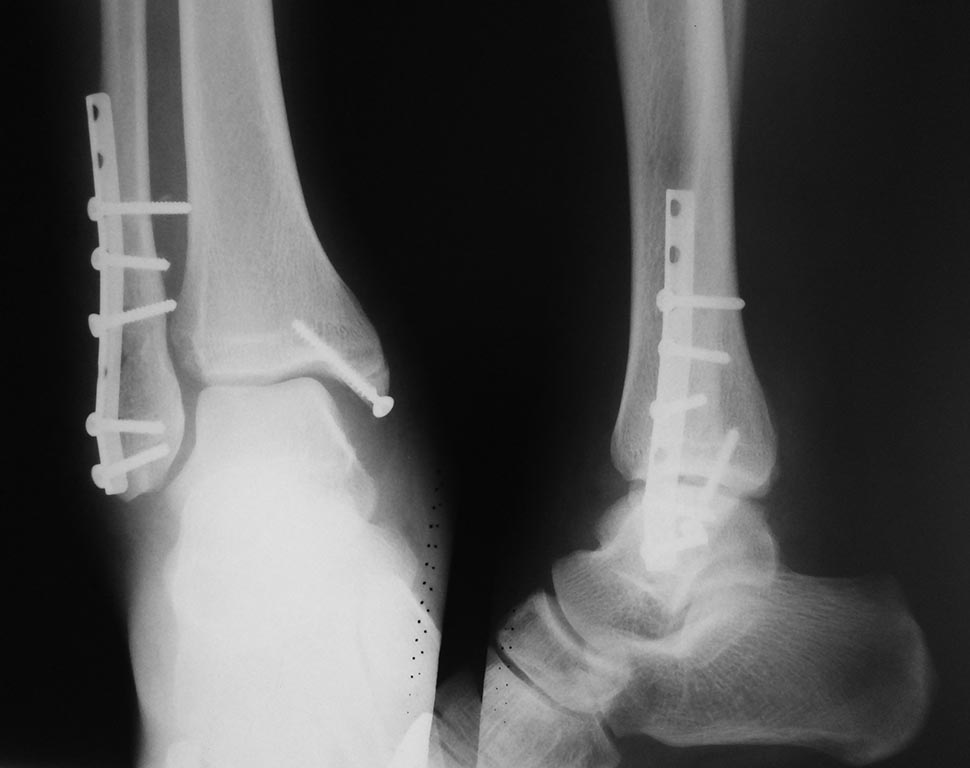

Здравствуйте, коллеги

Через послеоперационную рану удалил проксимальный винт, откусил кусачками пару миллиметров

Завтра попробую убрать верхний винт и провести позиционный винт или над пластиной, если получится .

Удалить 3 винт и через него ввести болт-стяжку или позиционный потоньше

В случае автора темы, перелом наружной лодыжки на уровне синдесмоза ( я называю это "чрезсиндесмозный" перелом лодыжки), и есть разрыв передней (по личному опыту) порции синдесмоза. Синдесмоз нестабилен, будет подвывих тарана. Это требует фиксации синдесмоза винтом. Винт проводится через малоберцовую кость в большеберцовую под углом 25-30* сзади наперед в фронтальной плоскости. Винт проводится горизонтально линии голеностопного сустава (я ее маркирую на коже). Обычно это делается через одно из отверстий пластины (бывает, что его приходится рассверлить до диаметра резьбы винта перед или в момент операции сверлом по металлу). Можно поставить винт вне пластины, используя шайбу или обрезок пластины с 1 отверстием (не выкидываю обрезки). Винт нужно стремиться расположить как можно ниже к суставу, но не ближе 1 см. Т.е. на уровне физиологичного синдесмоза.

Винт должен быть не зафиксирован в просверленном канале в малоберцовой кости, поэтому

берется винт с длинной шейкой или (если таковые не имеются вдруг) можно сделать канал в малоберцовой кости шире, чтоб резьба у головки не фиксировалась в стенках канала. Это динамическая фиксация. Это важно. В большеберцовой кости всегда фиксация в противоположном кортикале, иначе винт мигрирует, естественно. Нужно точно подобрать длину винта.

Не нужно затягивать винт изо всех своих мужских сил. Это ПОЗИЦИОННЫЙ винт. Подвывих устранен, и хватит. Тут легко вырабатывается мышечная память у хирурга. (У меня есть удобная С-дуга, иногда пользуюсь в конце операции.)

Винт нужно обязательно удалить перед разрешением ходьбы с полной нагрузкой на оперированную конечность. Я это делаю через 1,5 - 2 месяца и разрешаю переход с костылей на трость. Rg контроль через 3 мес. от операции. Остальные импланты снимаю через 6-12 мес. от операции.